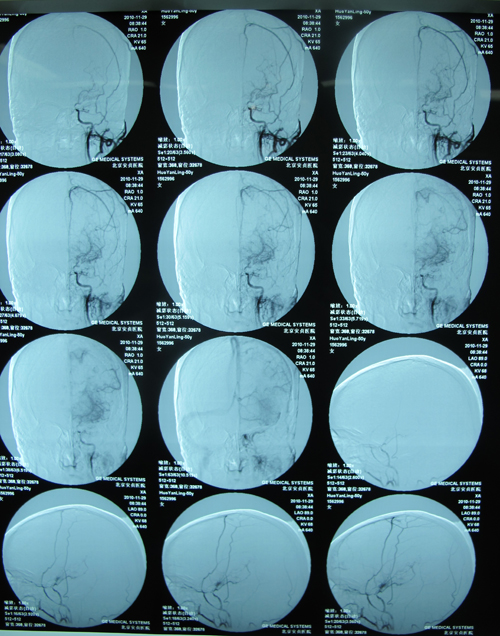

DSA示:右侧颈内动脉起始段90%狭窄,左侧颈内动脉管径全程较细,左侧大脑中动脉未显影,代之异常丰富毛细血管形成,右侧颈内动脉虹吸部异常 血管形成。

该患者右侧颈内动脉重度狭窄,有CEA或CAS指征。患者如果进行CAS,术后需用波立维、拜阿司匹林双抗半年到一年时间,由于该患者左侧大脑中动脉未显影,代之异常丰富毛细血管形成,术后长期服药过程中可能有出血危险。而CEA术后仅需口服拜阿司匹林,降低出血风险,且CEA适应证和远期疗效由于CAS,因此选择CEA治疗。